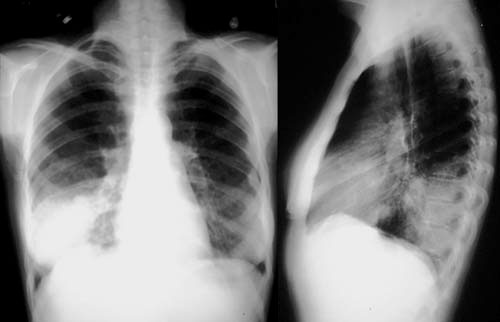

Pneumonia é um tipo de inflamação no peito. Existem vários tipos diferentes de inflamação no peito (incluindo bronquite), que podem variar em gravidade. A pneumonia pode ser causada por um agente bacteriano, vírico, fungico ou ter uma causa desconhecida. Atinge secundariamente os pequenos sacos aéreos (alvéolos) nos pulmões. Quando tem pneumonia, esses sacos de ar ficam cheios de líquido (imagem inferior) e isso dificulta o funcionamento adequado dos pulmões.

Os médicos geralmente diagnosticam pneumonia perguntando sobre os seus sintomas e examinando seu torax. Se estiver no hospital, uma radiografia de tórax é geralmente realizada para confirmar o diagnóstico.